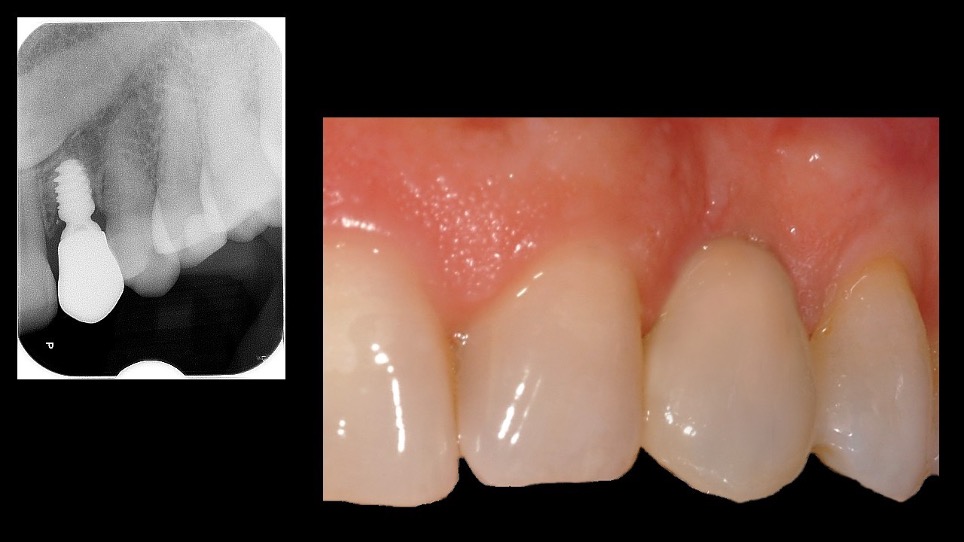

Di seguito vengono riportati due casi clinici emblematici, affrontati presso il Reparto di Parodontologia e Implantologia dell’Istituto Stomatologico Italiano, ove la progettazione digitale degli short implant si è rivelata indispensabile sia per minimizzare la morbilità del paziente sia per ottenere il successo clinico testimoniato dai follow-up. Nel primo caso viene trattata una paziente caucasica, 57 anni, che presenta i canini superiori inclusi; in seguito alla estrazione dell’elemento 6.3, si è resa necessaria la riabilitazione implanto-protesica del 2.3 (Figura 1).

Tuttavia, la paziente rifiutava l’estrazione del 2.3 incluso e pertanto è stato proposto un protocollo con short implant (Figure 2-3).